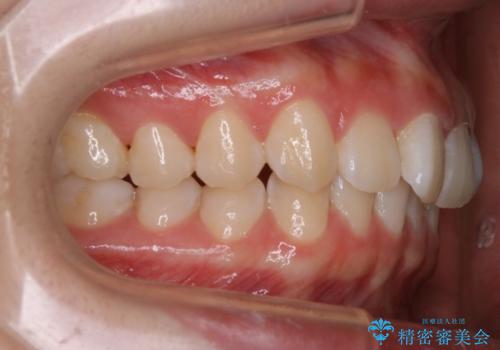

- 初診時、前歯のガタつきを主訴にご来院されました。

精密検査の結果奥歯の噛み合わせのズレからくる前歯のガタつきであることが分かり、患者様と相談した結果、全体をしっかりと治療することをご選択なさったので奥歯から動かして噛み合わせと見た目の両方を治す治療プランとなりました。

下顎の歯は幸いガタつきが少なかったため、下顎を基準とし構成する方針としました。